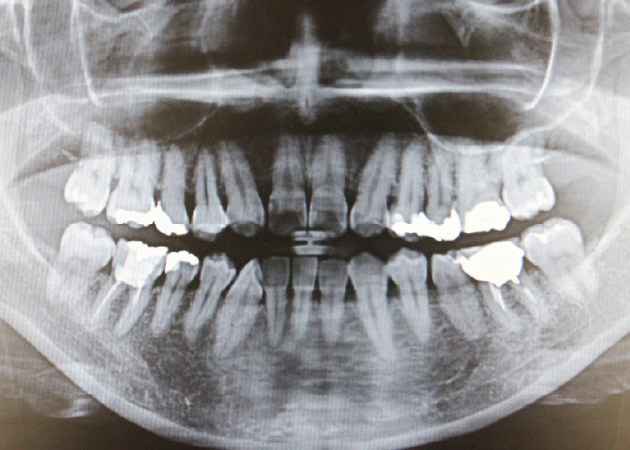

5. 05.レントゲン撮影

05.レントゲン撮影

必要に応じて、レントゲンを撮影し、歯を支える骨の状態を確認します。骨の吸収(骨の減少)が見られる場合、歯周病が進行していることが分かります。